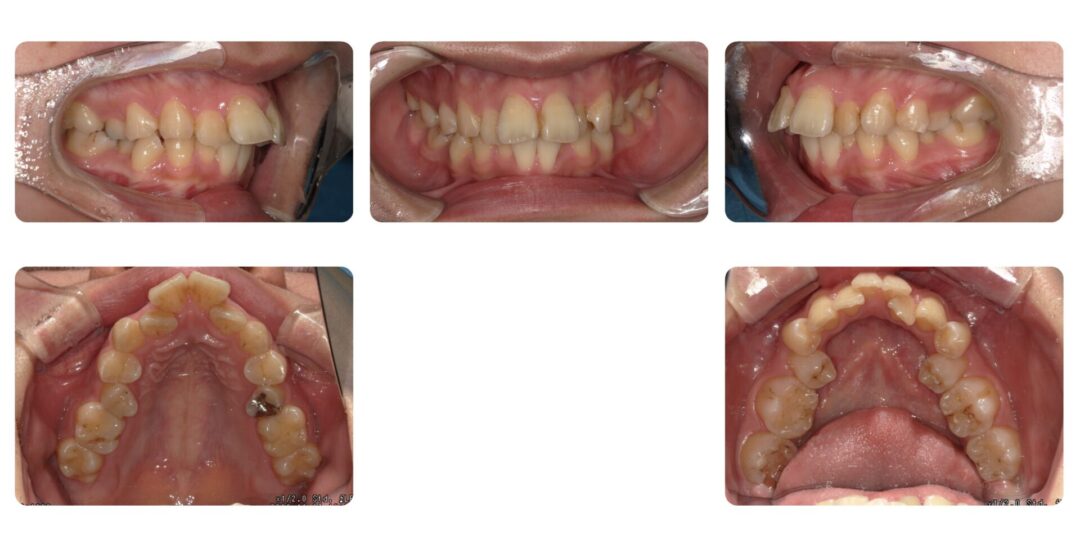

矯正治療前

前歯が出ている、上下歯が重なっているところがある

初診時24歳

成人矯正 上顎左右第一小臼歯、下顎左右第二抜歯 マルチブラケット矯正

4年1ヶ月